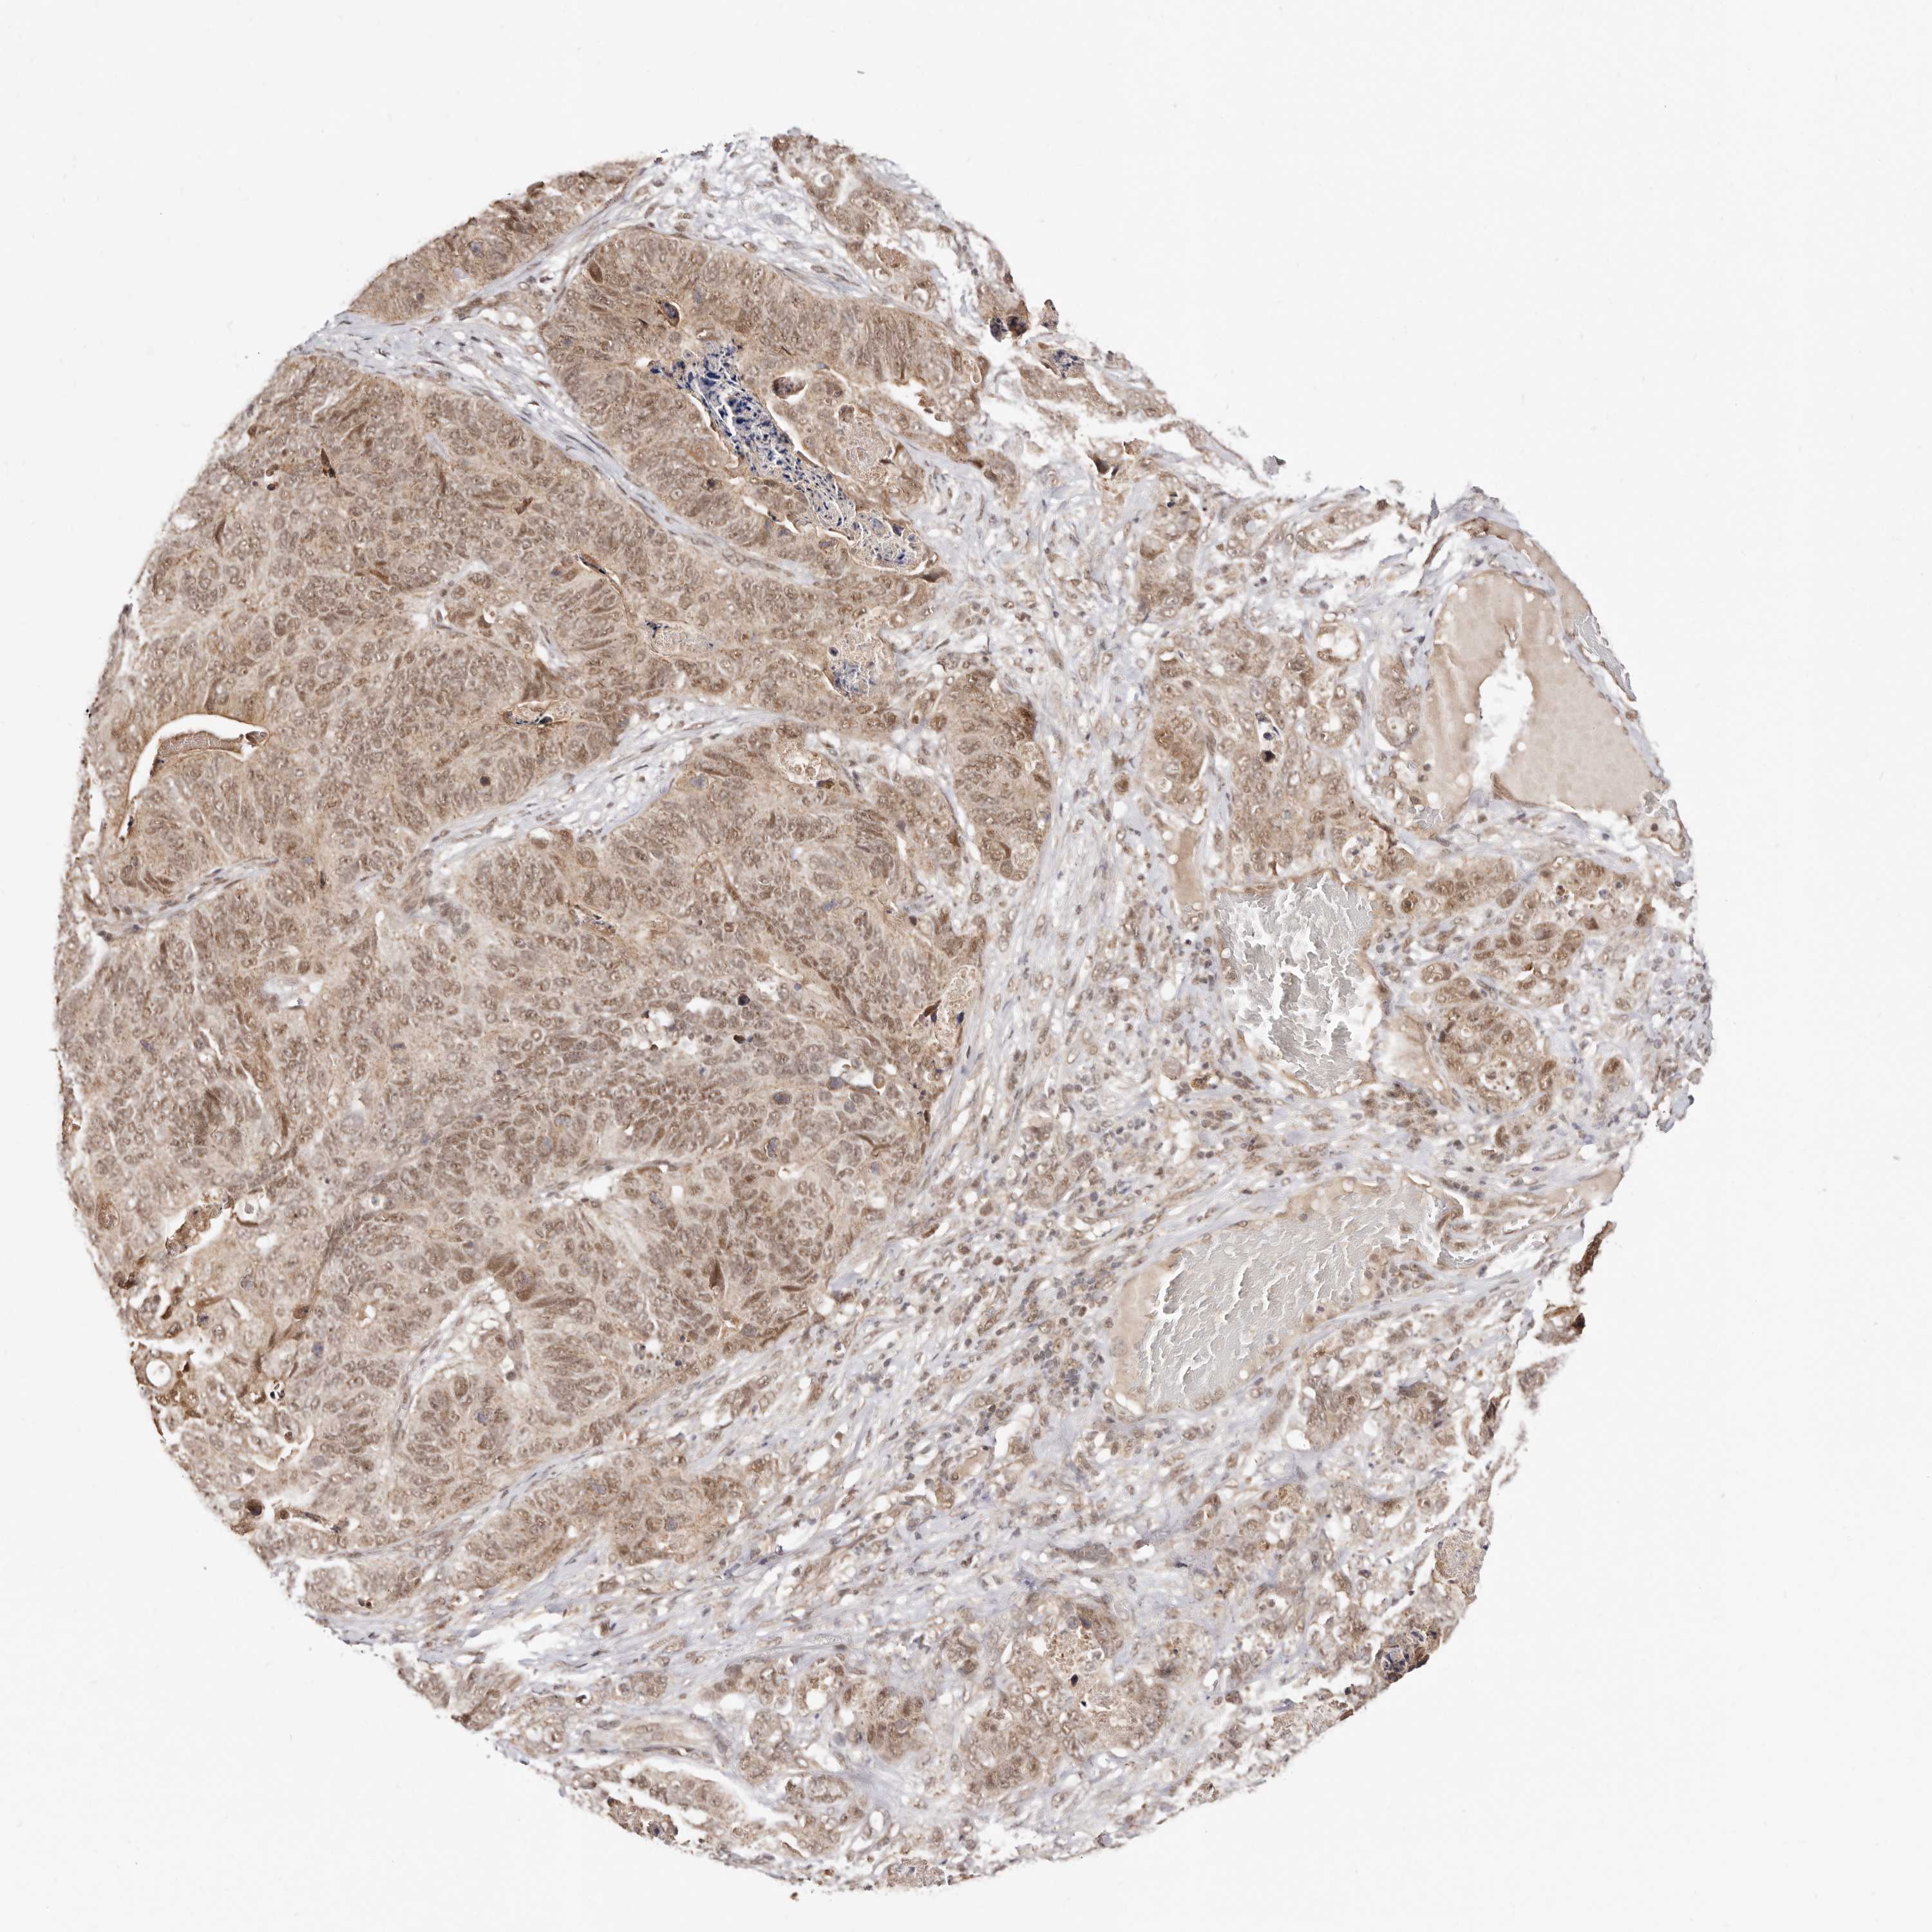

STOMACH CANCER - Protein expressioni

A mouse-over function shows sample information and annotation data. Click on an image to view it in a full screen mode. Samples can be filtered based on level of antibody staining by selecting one or several of the following categories: high, medium, low and not detected. The assay and annotation is described here.

Note that samples used for immunohistochemistry by the Human Protein Atlas do not correspond to samples in the TCGA dataset.

Antibody stainingi

Antibody staining in the annotated cell types in the current human tissue is reported as not detected, low, medium, or high, based on conventional immunohistochemistry profiling in selected tissues. This score is based on the combination of the staining intensity and fraction of stained cells.

Each image is clickable and will lead to virtual microscopy that enables deeper exploration of all samples and also displays staining intensity scores, fraction scores and subcellular localization as well as patient and tissue information for each sample.

Antibody HPA028377

Antibody HPA028438

Staining

High

Medium

Low

Not detected

Intensity

Strong

Moderate

Weak

Negative

Quantity

>75%

75%-25%

<25%

None

Location

Nuclear

Cytoplasmic/membranous

Cytoplasmic/membranous,nuclear

Adenocarcinoma, NOS